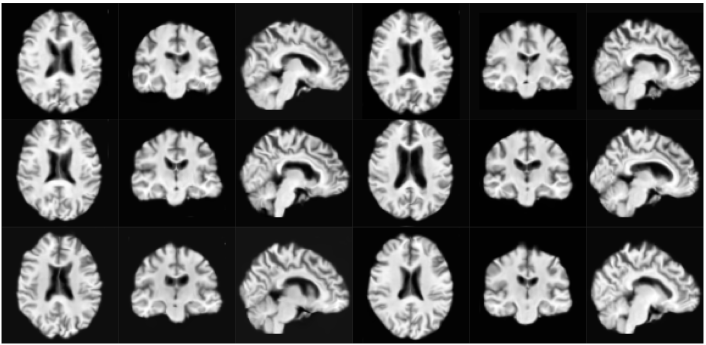

Qualitative analysis of the compared methods reveals that samples from VAE are not anatomically correct in many cases and display regions that appear scrambled. WGAN generates anatomically viable samples, however in many of them the cortical folds do not follow the anatomical structure. Additionally, as in VAE, samples exhibit regions where artifacts are dramatically different from the rest of the volume. Samples from our model are the most anatomically correct due to starting from the fixed template. However, the samples occasionally have a wavy visual quality due to improperly generated random deformation fields at finer scales. We furthermore observe a lack of sufficient topological diversity in the cortical folds. Samples for each of the above methods are shown in Section A of Supplementary Material.